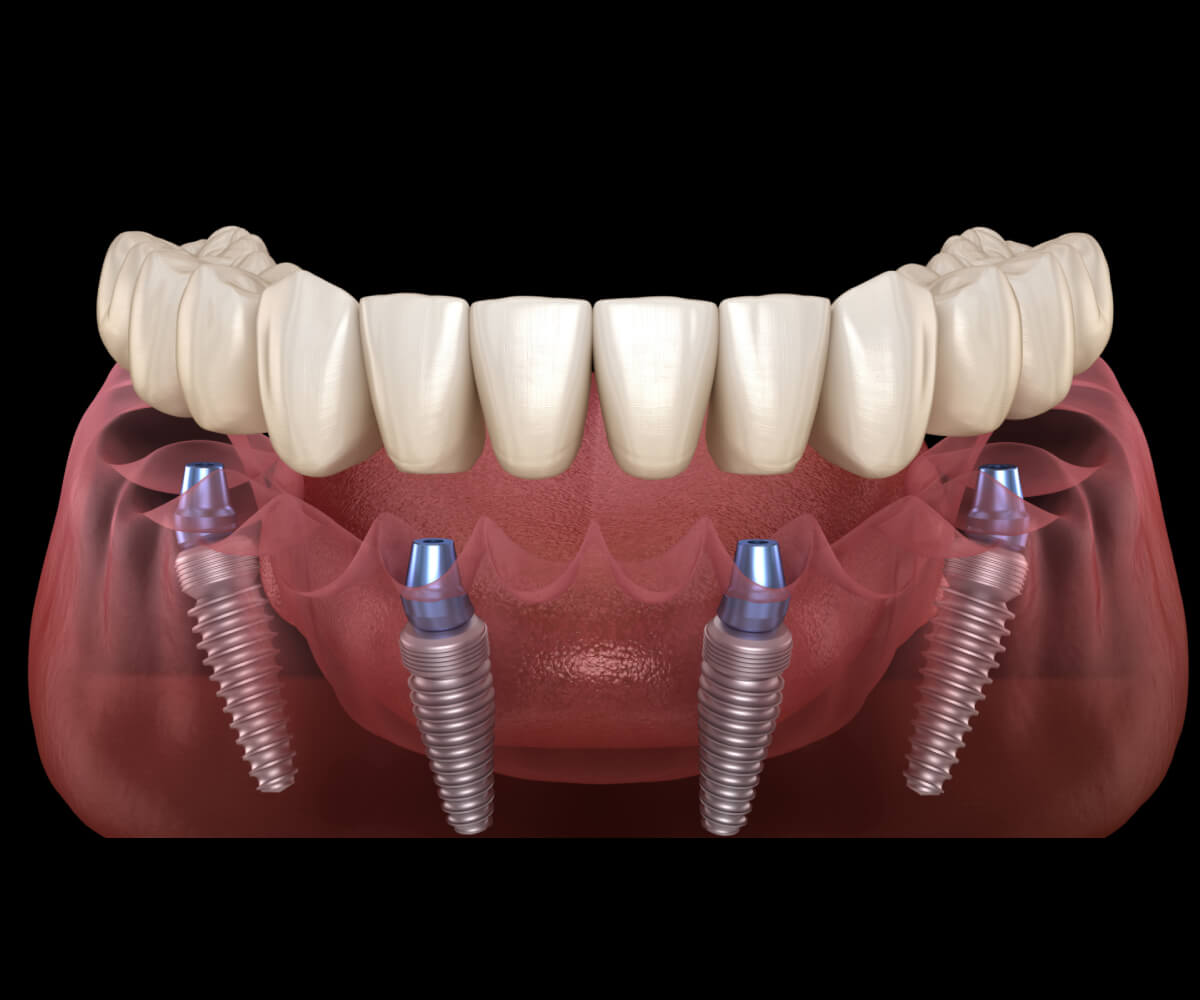

All Teeth On 4 implants provide a secure and efficient solution for replacing a full arch of missing teeth using four strategically placed implants. This treatment restores smile function, stability, and confidence with a natural-looking full-arch restoration.